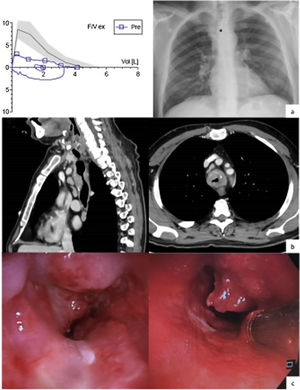

We present a 51-year-old man, an active smoker with a cumulative smoking rate of 50 pack-years and consumer of 80g of alcohol per day. His clinical record showed essential hypertension and hepatic steatosis. For several months he had experienced shortness of breath, oppressive chest pain, cough – sometimes accompanied by bloody sputum –, hoarseness, dysphonia and, later on, inspiratory stridor. The blood test and the arterial gasometry run in the emergency room showed polyglobulia and hypercapnic respiratory insufficiency. Initially, the patient was hospitalized in the respiratory ward and a spirometry and a chest X-ray were performed (Fig. 1a). The former proved a severe obstruction of the airway and a flattened expiratory phase in the flow-volume loop. As his condition worsened, he was admitted in the intermediate respiratory care unit and received non-invasive mechanical ventilation. A computerized thoracic tomography revealed a tracheal lesion that infiltrated its wall from its first ring to the carina, compromised 85% of its lumen and was in close relation with the aorta and the esophagus, as well as multiple adenopathies (Fig. 1b). A bronchoscopy was performed and a tumor with focal necrosis was removed (Fig. 1c). The anatomophatology analysis identified it as a small cell carcinoma. The cancer was staged as T4N2M0 (stage IV) after an extended radiological study. A second bronchoscopy was carried out in order to place a prothesis to lessen the symptoms caused by the obstruction. The patient is currently undergoing radiotherapy combined with cisplatin-based chemotherapy.